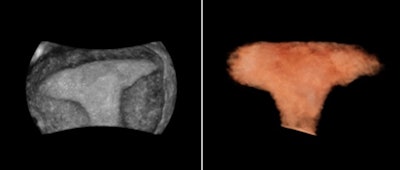

In gynecology, 3D ultrasounds can be helpful in many circumstances, including but not limited to evaluating the relationship of masses in the endometrial cavity, identifying uterine congenital anomalies and a thickened and/or heterogeneous endometrium, and evaluating the location of an intrauterine device and the integrity of the pelvic floor, according to Benacerraf and guidelines found in the 2014 American Institute of Ultrasound in Medicine (AIUM) practice parameter "Ultrasound of the Female Pelvis." Specifically, uterus malformations such as a bicornuate, or heart-shaped, uterus can be easily evaluated with 3D, Benacerraf said at the 2012 ISUOG meeting.